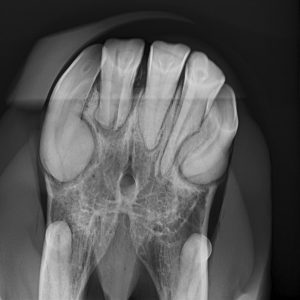

Top-Thema: Pferdezähne

- Pferdezähne sind anders…Perfekte Anpassung an die Nahrung

- Gut Zahn!? Zahnprobleme erkennen und behandeln

- EOTRH: Die mysteriöse Zahnerkrankung